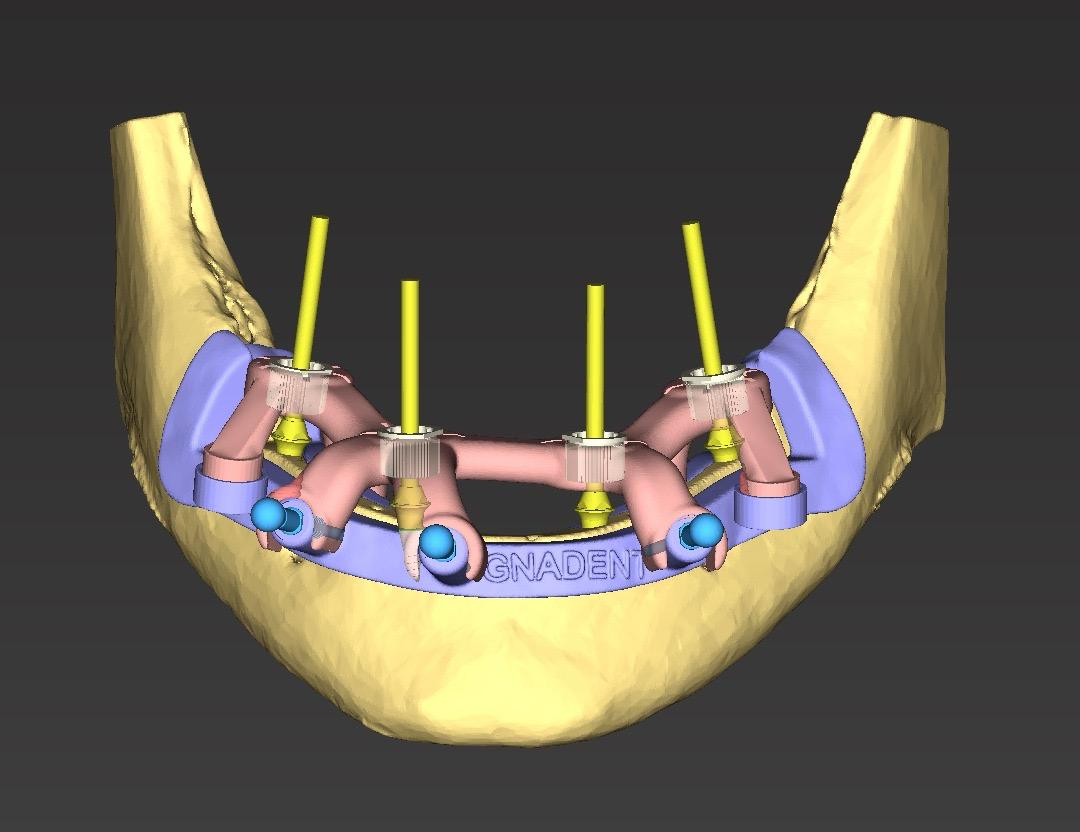

Protocolo de Precisión Digital

Hemos eliminado la improvisación. Cada paso de tu tratamiento está digitalizado para maximizar la seguridad, reducir tiempos y mejorar tu confort.

Diagnóstico y Escáner 3D

Realizado por el Dr. Company o la Dra. Chuliá. Te entregamos un plan de tratamiento completo y digitalizado, sin compromisos.

Planificación Digital

Analizamos tu caso en software 3D antes de tocarte. Diseñamos la posición exacta de cada implante o carilla para garantizar la estética y función perfectas.

Cirugía Guiada

Gracias a la impresión 3D de férulas quirúrgicas, colocamos los implantes en la posición exacta planificada. Mínimamente invasivo, a menudo sin puntos de sutura.